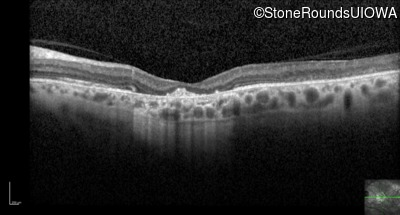

Optical Coherence Tomography - Right - 20/125 -2

Exemplar / OCT Stack

OCT Stack